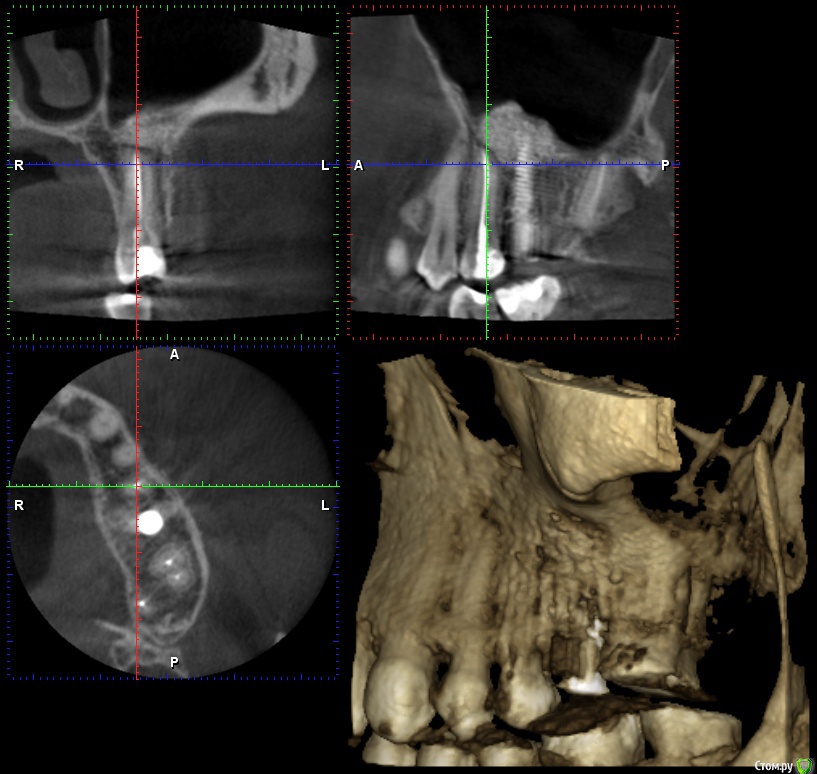

wladdX Опубликовано 26 января, 2017 Поделиться Опубликовано 26 января, 2017 Несколько скринов 2-й сегмент. Ссылка на комментарий

wladdX Опубликовано 26 января, 2017 Поделиться Опубликовано 26 января, 2017 (изменено) 3-й сегмент. Изменено 26 января, 2017 пользователем wladdX Ссылка на комментарий